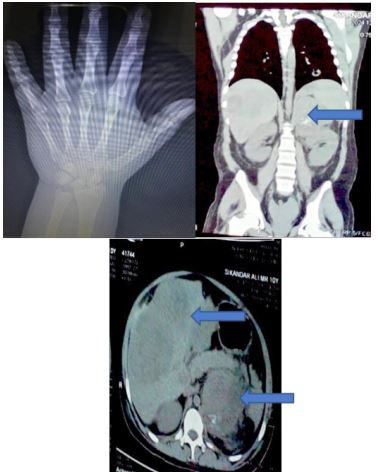

His labs are summarized in table 01 and 02. That shows Pancytopenia, Aki, Hypokalemia, hypocalcemia, deranged LFts. Imaging revealed left adrenal mass with altered echotexture of liver and multiple hypoechoic areas, which were confirmed on CT imaging are possibly metastatic lesions involving lungs also (Figure 2b,2c) and x-ray wrist revealed advanced bone age of 14 years > Chronological age of 10 years (Figure 2a)

Figure 2: (a) All carpals and pisiform are ossified, growth plates of phalanges are fused, growth plates of distal radius and ulna are visualized. Bone age at 14 years > Chronological Age (10 years).

(2b) Left Adrenal (supra renal) Mass.

(2c) Left Adrenal mass and liver Mets.